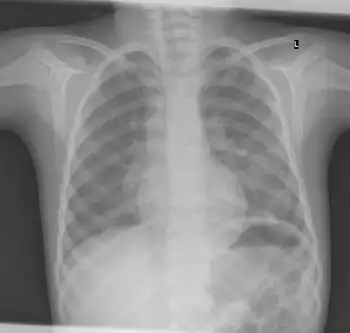

X-ray ribs: multiple enchondroma